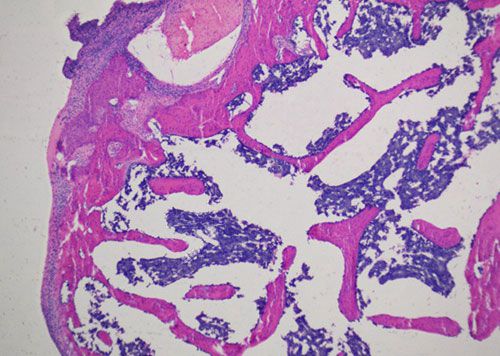

蘇木精-伊紅染色法 ( hematoxylin-eosin staining ),簡稱HE染色法,石蠟切片技術里常用的染色法之一,也可以用于未脫鈣骨硬組織切片。蘇木精染液為堿性,主要使細胞核內的染色質與胞質內的核糖體著紫藍色,伊紅為酸性染料,主要使細胞質和細胞外基質中的成分著紅色。HE染色法是組織學、胚胎學、病理學教學與科研中最基本、使用最廣泛的技術方法。

未脫鈣大鼠股骨HE染色